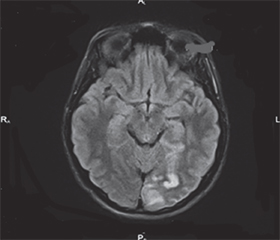

В огляді літератури показано, що ішемічний інсульт в осіб молодого віку становить 10–15 % серед усіх вікових груп. Серед етіологічних факторів ризику найбільш важливе місце займають артеріальна гіпертензія, аномалії розвитку судин, генетично зумовлені фактори — при патології серця (порушення ритму і провідності, відкрите овальне вікно), нирок. Наприклад, щорічний приріст ішемічного інсульту в осіб молодого віку відмічається за рахунок дисекції екстракраніальних артерій (на 2,4 в розрахунку на 100 тис. населення). Важливу роль відіграють антифосфоліпідний синдром, кардіальна емболія в результаті тромботичних уражень клапанів серця, гострого інфаркту міокарда, вади міжшлуночкової або міжпередсердної перегородки, васкуліти, зумовлені різними інфекційними та системними захворюваннями, хвороба мойя-мойя, мітохондріальні енцефалопатії, гіпергомоцистеїнемія, вроджена патологія магістральних артерій голови і шиї (подовження, перегин, петлеутворення). Виокремлено фактори ризику, зокрема, наявність мігрені з аурою, вживання естрогенвмісних оральних контрацептивів, тютюнокуріння, вживання алкоголю у великих кількостях та наркотиків. Описані основні протромботичні стани, що асоціюються з розвитком ішемічного інсульту в осіб молодого віку, — вагітність та післяпологовий період, перенесений COVID-19, онкопатологія. Таким чином, визначено багатофакторність розвитку інсульту в осіб молодого віку. Висвітлено питання діагностики з використанням інструментальних і лабораторних досліджень. Описаний клінічний випадок атеротромботичного ішемічного інсульту у пацієнта молодого віку з власної практики.

The literature review demonstrates that ischemic stroke in young adults accounts for 10–15 % in all age groups. Among the etiological risk factors, the most significant are hypertension, vascular developmental anomalies, and genetically determined factors — particularly in cases of heart pathology (rhythm and conduction disorders, patent foramen ovale) and kidney di-seases. For example, the annual increase in ischemic stroke among young adults is attributed to extracranial artery dissection, with a 2.4-fold rise per 100,000 population. An important role is played by antiphospholipid syndrome, cardiac embolism resulting from thrombotic lesions of the heart valves, acute myocardial infarction, ventricular or atrial septal defects, vasculitis caused by various infectious and systemic diseases, moyamoya disease, mitochondrial encephalopathies, hyperhomocysteinemia, and congenital pathology of the major arteries of the head and neck (elongation, kinking, looping). Identified risk factors include the presence of migraine with aura, the use of estrogen-containing oral contraceptives, smoking, excessive alcohol consumption, and drug use. The main prothrombotic conditions associated with the development of ischemic stroke in young adults are described, including pregnancy and the postpartum period, a history of COVID-19, and cancer. Thus, the multifactorial nature of stroke development in young adults has been identified. The review highlights diagnostic approaches using instrumental and laboratory investigations. A clinical case of atherothrombotic ischemic stroke in a young patient from personal practice is described.